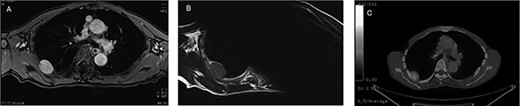

An asymptomatic 79-year-old male who was diagnosed with a chest wall tumor, which had been detected by an X-ray of a health examination, presented to our hospital for surgical intervention. He had no relevant past medical history, including malignant neoplasm or radiation therapy. No mass was palpable. The chest X-ray revealed a tumor shadow of 3 cm in diameter in the right upper lung field (Fig. 1). Chest contrast computed tomography (CT) revealed a well-circumscribed tumor shadow measuring 37 × 27 mm in the posterolateral region of the right sixth intercostal space, the size of which had increased 1.5 times in the previous 3 months (Fig. 2). Thoracic magnetic resonance imaging (MRI) revealed a solid tumor that was enhanced by gadolinium on T1-weighted imaging (T1WI). T2-weighted imaging (T2WI) showed a homogeneous mass with iso-intensity. The tumor was inhomogeneous while demonstrating a maximum standardized uptake value (SUV) of the [18F]-2-deoxy-D-glucose (FDG) uptake under positron emission tomography (PET), with a range of 3.4–4.1 (Fig. 3). There was no significant uptake at other sites, including the mediastinal lymph nodes. No tumor-markers (CEA, proGRP and CYFRA) were detected in a laboratory analysis. Based on these examinations, we suspected a neurogenic tumor, especially schwannoma, and we opted for surgical resection. Considering the fact that ~10% of neurogenic tumors are malignant and the FDG uptake was heterogeneous, we planned to perform an intraoperative frozen section examination. We first performed tumor resection. The operation was performed in the left lateral position under general anesthesia. A 30° viewing angle thoracoscope was set at the middle axillary line of the seventh intercostal space. The tumor was smooth, slightly solid and covered with pleura (Fig. 4). We added a 4-cm incision just above the tumor, while verifying its location through the thoracoscope, and easily removed it from the chest wall. The tumor was diagnosed as sarcoma based on the frozen section examination. Therefore, we added removal of a portion of the sixth and seventh right rib. We excised the chest wall with a 2-cm margin from the lesion, confirming an adequate length through the thoracoscope. Chest wall reconstruction was performed with DUALMESH® (Gore, Flagstaff, AZ). On the cut section, the tumor appeared as solid, smooth-surfaced and encapsulated whitish mass of 3.7 × 2.7 cm in size. Upon microscopic examination, the tumor was composed of fascicles of highly atypical spindle cells mitotic figures exceeding 15 per 10 high-power fields. Immunohistochemistry was positive for αSMA (Fig. 5), desmin and caldesmon and was negative for S-100 protein (data not shown). All margins were negative, and no invasion to the peripheral organs was seen. We concluded that the tumor was leiomyosarcoma of the chest wall. He was discharged on post-operative day 10 without any complications. Since we considered that curative resection had been achieved, no adjuvant therapy was performed. He is still being followed up; however, liver and multiple lung metastases were detected at 5 years after surgery.

Preoperative MRI and PET-CT: (A) contrast-enhanced T1WI: hyper-intense; (B) T2WI: iso-intense; (C) PET-CT: SUVmax 3.4–4.1.

On CT, thoracic leiomyosarcomas are usually characterized by huge soft tissue masses with heterogeneous enhancement because of bleeding, necrosis and other heterogeneous textures. Larger tumors can also push against the surrounding organs and can occasionally be invasive [6)]. Leiomyosarcomas show enhancement on MRI, while they also show a high FDG uptake on PET-CT [7]. Alternatively, schwannoma shows a smooth tumor with homogeneous enhancement on CT. Schwannomas may be heterogeneous due to necrosis or hemorrhage within the mass. On MRI, the tumor is iso- to hypo-intense, while it is also enhanced with contrast media on T1WI and is iso- to hyper-intense on T2WI [8]. The administration of gadolinium causes homogeneous enhancement [9]. In this case, homogeneous enhancement with gadolinium and a clear border were similar to the characteristics of schwannoma. The heterogeneous FDG uptake on PET-CT and rapid growth of tumor were the only findings that raised the suspicion of malignancy.